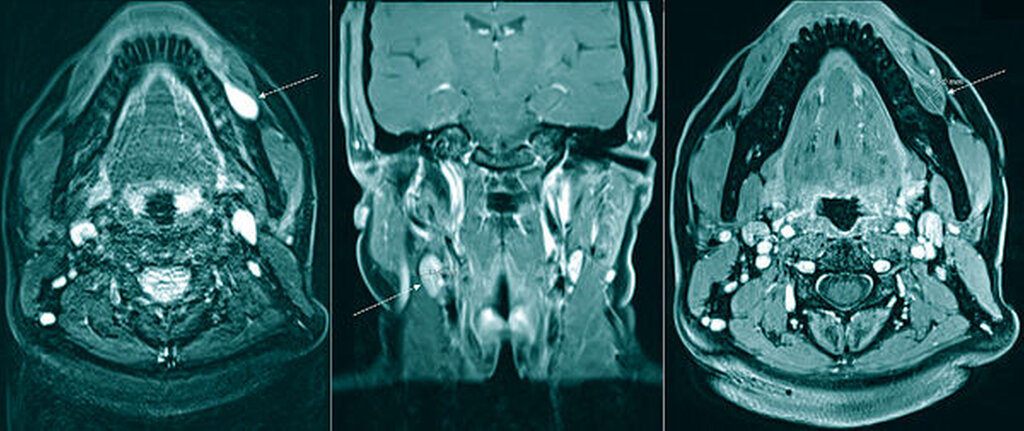

Ein mit Kontrastmittel durchgeführtes MRT ergab den bildmorphologischen Befund einer dem linken Alveolarknochen von vestibulär angelagerten, kontrastmittelanreichernden, vaskulären Anomalie (hyperintense Struktur entlang des Alveolarfortsatzes in der T1-Wichtung; Abbildung 2). Aufgrund des Patientenwunsches nach Entfernung und des zunehmenden Blutungsrisikos bei fortschreitender Größenprogredienz erfolgte die Resektion des Befunds bereits in der darauffolgenden Woche in Allgemeinanästhesie.